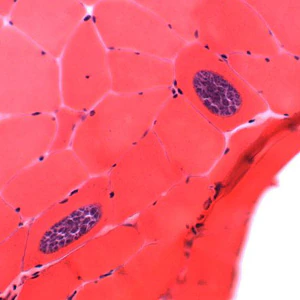

Sarcocystis sarcocysts in tissue.

For intestinal sarcocystosis caused by S. hominis and S. suihominis, diagnosis is made by the observation of oocysts or sporocysts in stool. They are easily overlooked as they are often shed in small numbers. Also, the two species cannot be separated by oocyst or sporocyst morphology. When humans serve as dead-end hosts for non-human Sarcocystis spp., diagnosis is made by the finding of sarcocysts in tissue specimens.